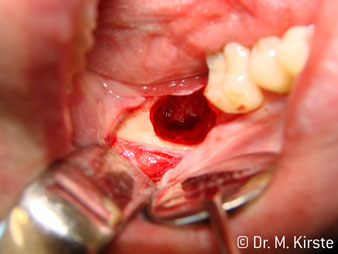

The 45° angle of the handpiece has been specially selected for its wide range of advantages. Colleagues who work in surgery, and for whom this handpiece was primarily developed, will soon appreciate the ability to work efficiently in very restricted spaces. In wisdom tooth extractions in particular (fig. 2) there is no need for large-scale spreading of the soft tissues in the cheek region (fig. 3). The design of the handpiece head combined with turning the head slightly during preparation allows work to be carried out quickly and safely in the retromolar region.